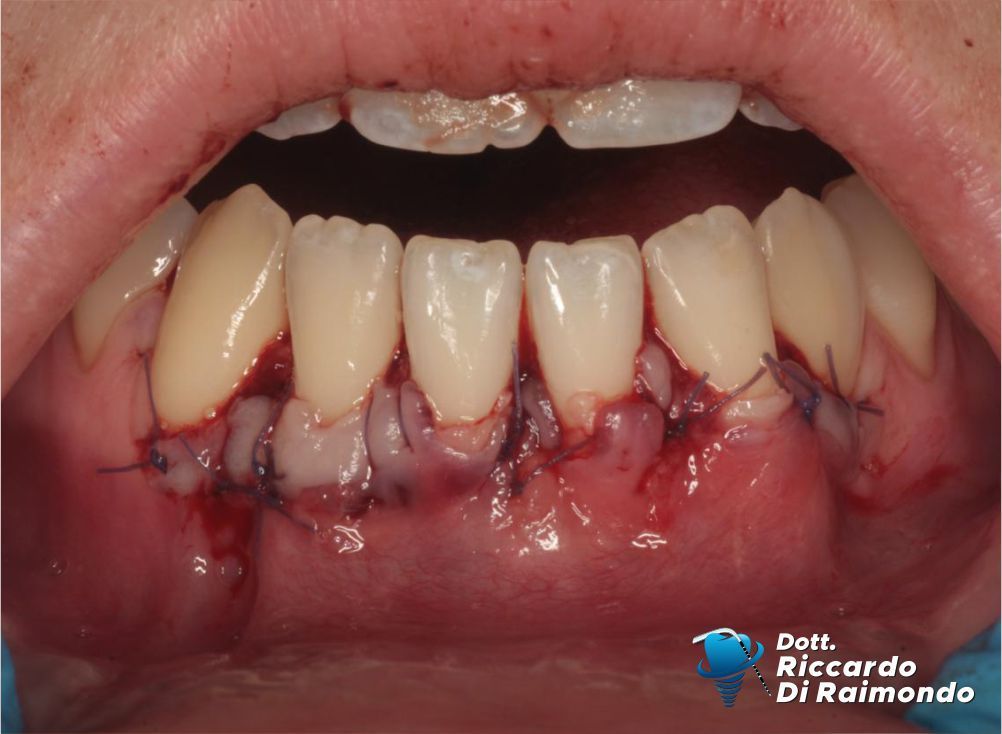

La procedura chirurgica ha previsto il prelievo di un innesto di tessuto connettivo dal palato, successivamente utilizzato per aumentare lo spessore dei tessuti nell’area interessata. La copertura delle recessioni è stata quindi eseguita mediante una tecnica di avanzamento coronale modificato, particolarmente indicata nel trattamento delle recessioni multiple.

Durante il Trattamento